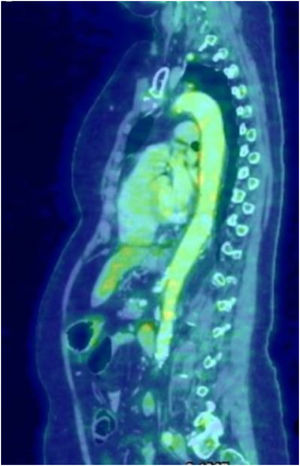

La arteritis de células gigantes (ACG) es una vasculitis granulomatosa que afecta las arterias de mediano y gran calibre, más común en individuos mayores de 50 años. El espectro clínico es amplio, y abarca las manifestaciones clásicas como cefalea, claudicación mandibular, alteraciones visuales y polimialgia reumática, hasta diversas manifestaciones atípicas. En un 10-15%, la ACG afecta a la aorta y sus ramas; la región del cayado aórtico y la aorta torácica son las zonas más afectadas, siendo infrecuente el compromiso de la aorta en toda su extensión1. Por otro lado, el compromiso aórtico se ha descripto en más de un 50% de los PET realizados a pacientes con diagnóstico confirmado de ACG2. Presentamos el caso de una mujer de 69 años, sin antecedentes patológicos que consultó por un episodio autolimitado de paresia braquiocrural izquierda, asociado con historia de claudicación mandibular de 15 días de evolución, astenia, pérdida de 8kg de peso y dolor en cinturas escapular y pelviana en el último mes. En el laboratorio se destacaba aumento de la velocidad de sedimentación globular (VSG): 80mm/primera hora. La RM de encéfalo, la angio-TAC de vasos intra y extracraneales, el ecocardiograma y la ecografía doppler de arterias temporales no mostraron alteraciones de significación. Ante la sospecha de ACG se solicitó PET (fig. 1) marcado con 18-fluorodesoxiglucosa (FDG-PET), que mostró aumento heterogéneo de la actividad metabólica en las paredes de la arteria aorta en toda su extensión, arterias subclavias, carótidas primitivas bilaterales y, en menor medida, arterias ilíacas primitivas bilaterales. La paciente fue tratada inicialmente con dosis altas de corticoides asociados a metotrexato con pobre respuesta, por lo cual se le administró tocilizumab presentando mejoría de los síntomas y descenso marcado de la VSG. Los pacientes con ACG extracraneal frecuentemente presentan un cuadro clínico inespecífico. Debido a esto y a la baja sensibilidad de la biopsia temporal, habitualmente el diagnóstico se realiza por PET, RM o angiotomografía. Puntualmente la utilización del FDG-PET ha facilitado la evaluación de la inflamación de grandes vasos, con un alto grado de sensibilidad para detectar formas extracraneales, siendo el método de preferencia en pacientes con síntomas atípicos, y resultando de mucha utilidad para excluir otras enfermedades como malignidad3. El diagnóstico diferencial es muy amplio, y puede ser difícil diferenciarla de aquellos pacientes añosos con arteritis de Takayasu. En este sentido el FDG-PET puede ser de utilidad ya que en la ACG la distribución de la lesión aórtica es difusa y distal, con afectación de la aorta abdominal y sus ramas descendentes, y leves cambios morfológicos de la pared vascular, mientras que en la arteritis de Takayasu la distribución es segmentaria y con mayores cambios morfológicos4. Por otro lado, varias enfermedades pueden simular a las vasculitis de grandes vasos debido a la presencia de síntomas constitucionales o por la formación de aneurismas o estenosis en la aorta o sus ramas. Deben excluirse todas las causas de aortitis. Entre las infecciosas, los aneurismas micóticos, la sífilis e infecciones por micobacterias. Además, la inflamación de la arteria aorta se puede producir ocasionalmente en vasculitis asociadas a ANCA, enfermedad de Behçet, espondilitis anquilosante, sarcoidosis, síndrome de Sjögren y enfermedad por IgG4. La aterosclerosis siempre se debe considerar en el diagnóstico diferencial. Finalmente, la aortitis se puede encontrar aislada y ser idiopática5. Las complicaciones consisten en aneurisma o disección principalmente de la aorta ascendente, síndrome del arco aórtico, claudicación de miembros y accidente cerebrovascular1. En relación con el tratamiento se aplican las mismas estrategias que en aquellos pacientes con arteritis de la temporal6, si bien se ha visto que la enfermedad tiende a ser más refractaria7.